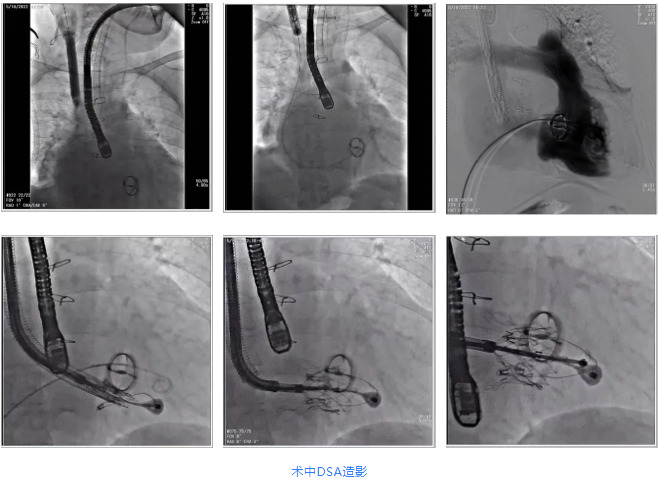

根據(jù)術前評估結果,郭應強教授團隊為患者量身定制了手術策略,決定使用LuX-Valve Plus經(jīng)血管三尖瓣置換系統(tǒng)開展手術治療。手術在全麻下進行,采用經(jīng)右側頸靜脈入路,在經(jīng)食道超聲和DSA的指引下調(diào)整輸送器角度以達到正確位置,勾住前瓣后逐步釋放盤片,盤片打開后順利扎針,最終完成瓣膜植入,輸送器撤出。術后超聲提示人工三尖瓣同軸性良好,瓣架固定牢靠,無反流和瓣周漏,術后三尖瓣平均跨瓣壓差為1 mmHg。